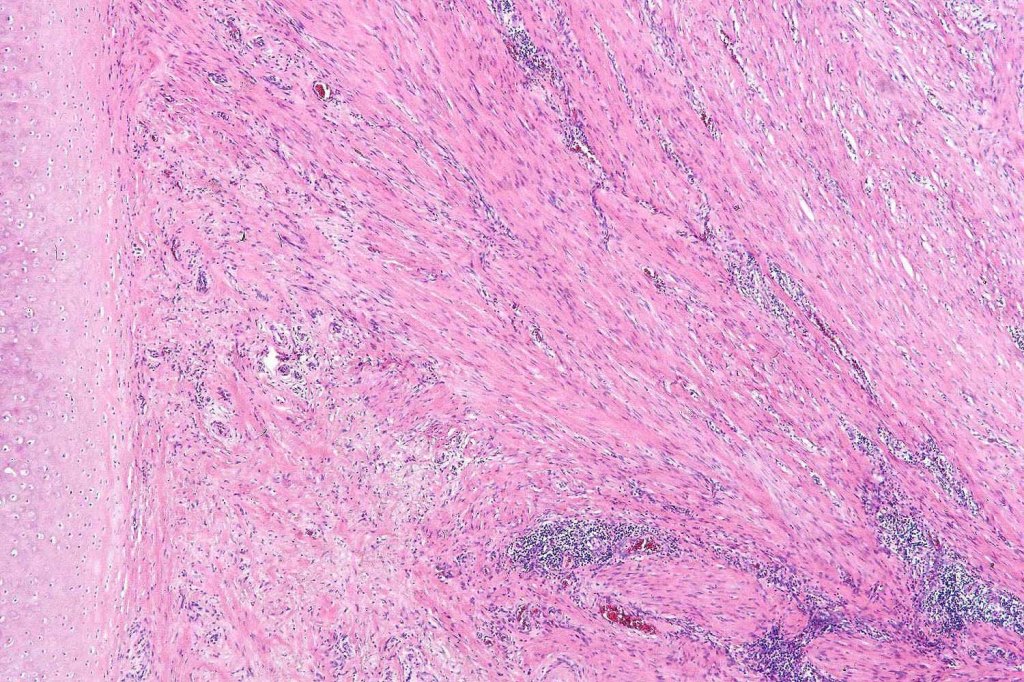

•Paucicellular spindle cell infiltrate with “myxoid” fine to a dense collagenous stroma

•Hyperchromatic nuclei

•Variable pleomorphism

•Neurotropism

•Neural transformation